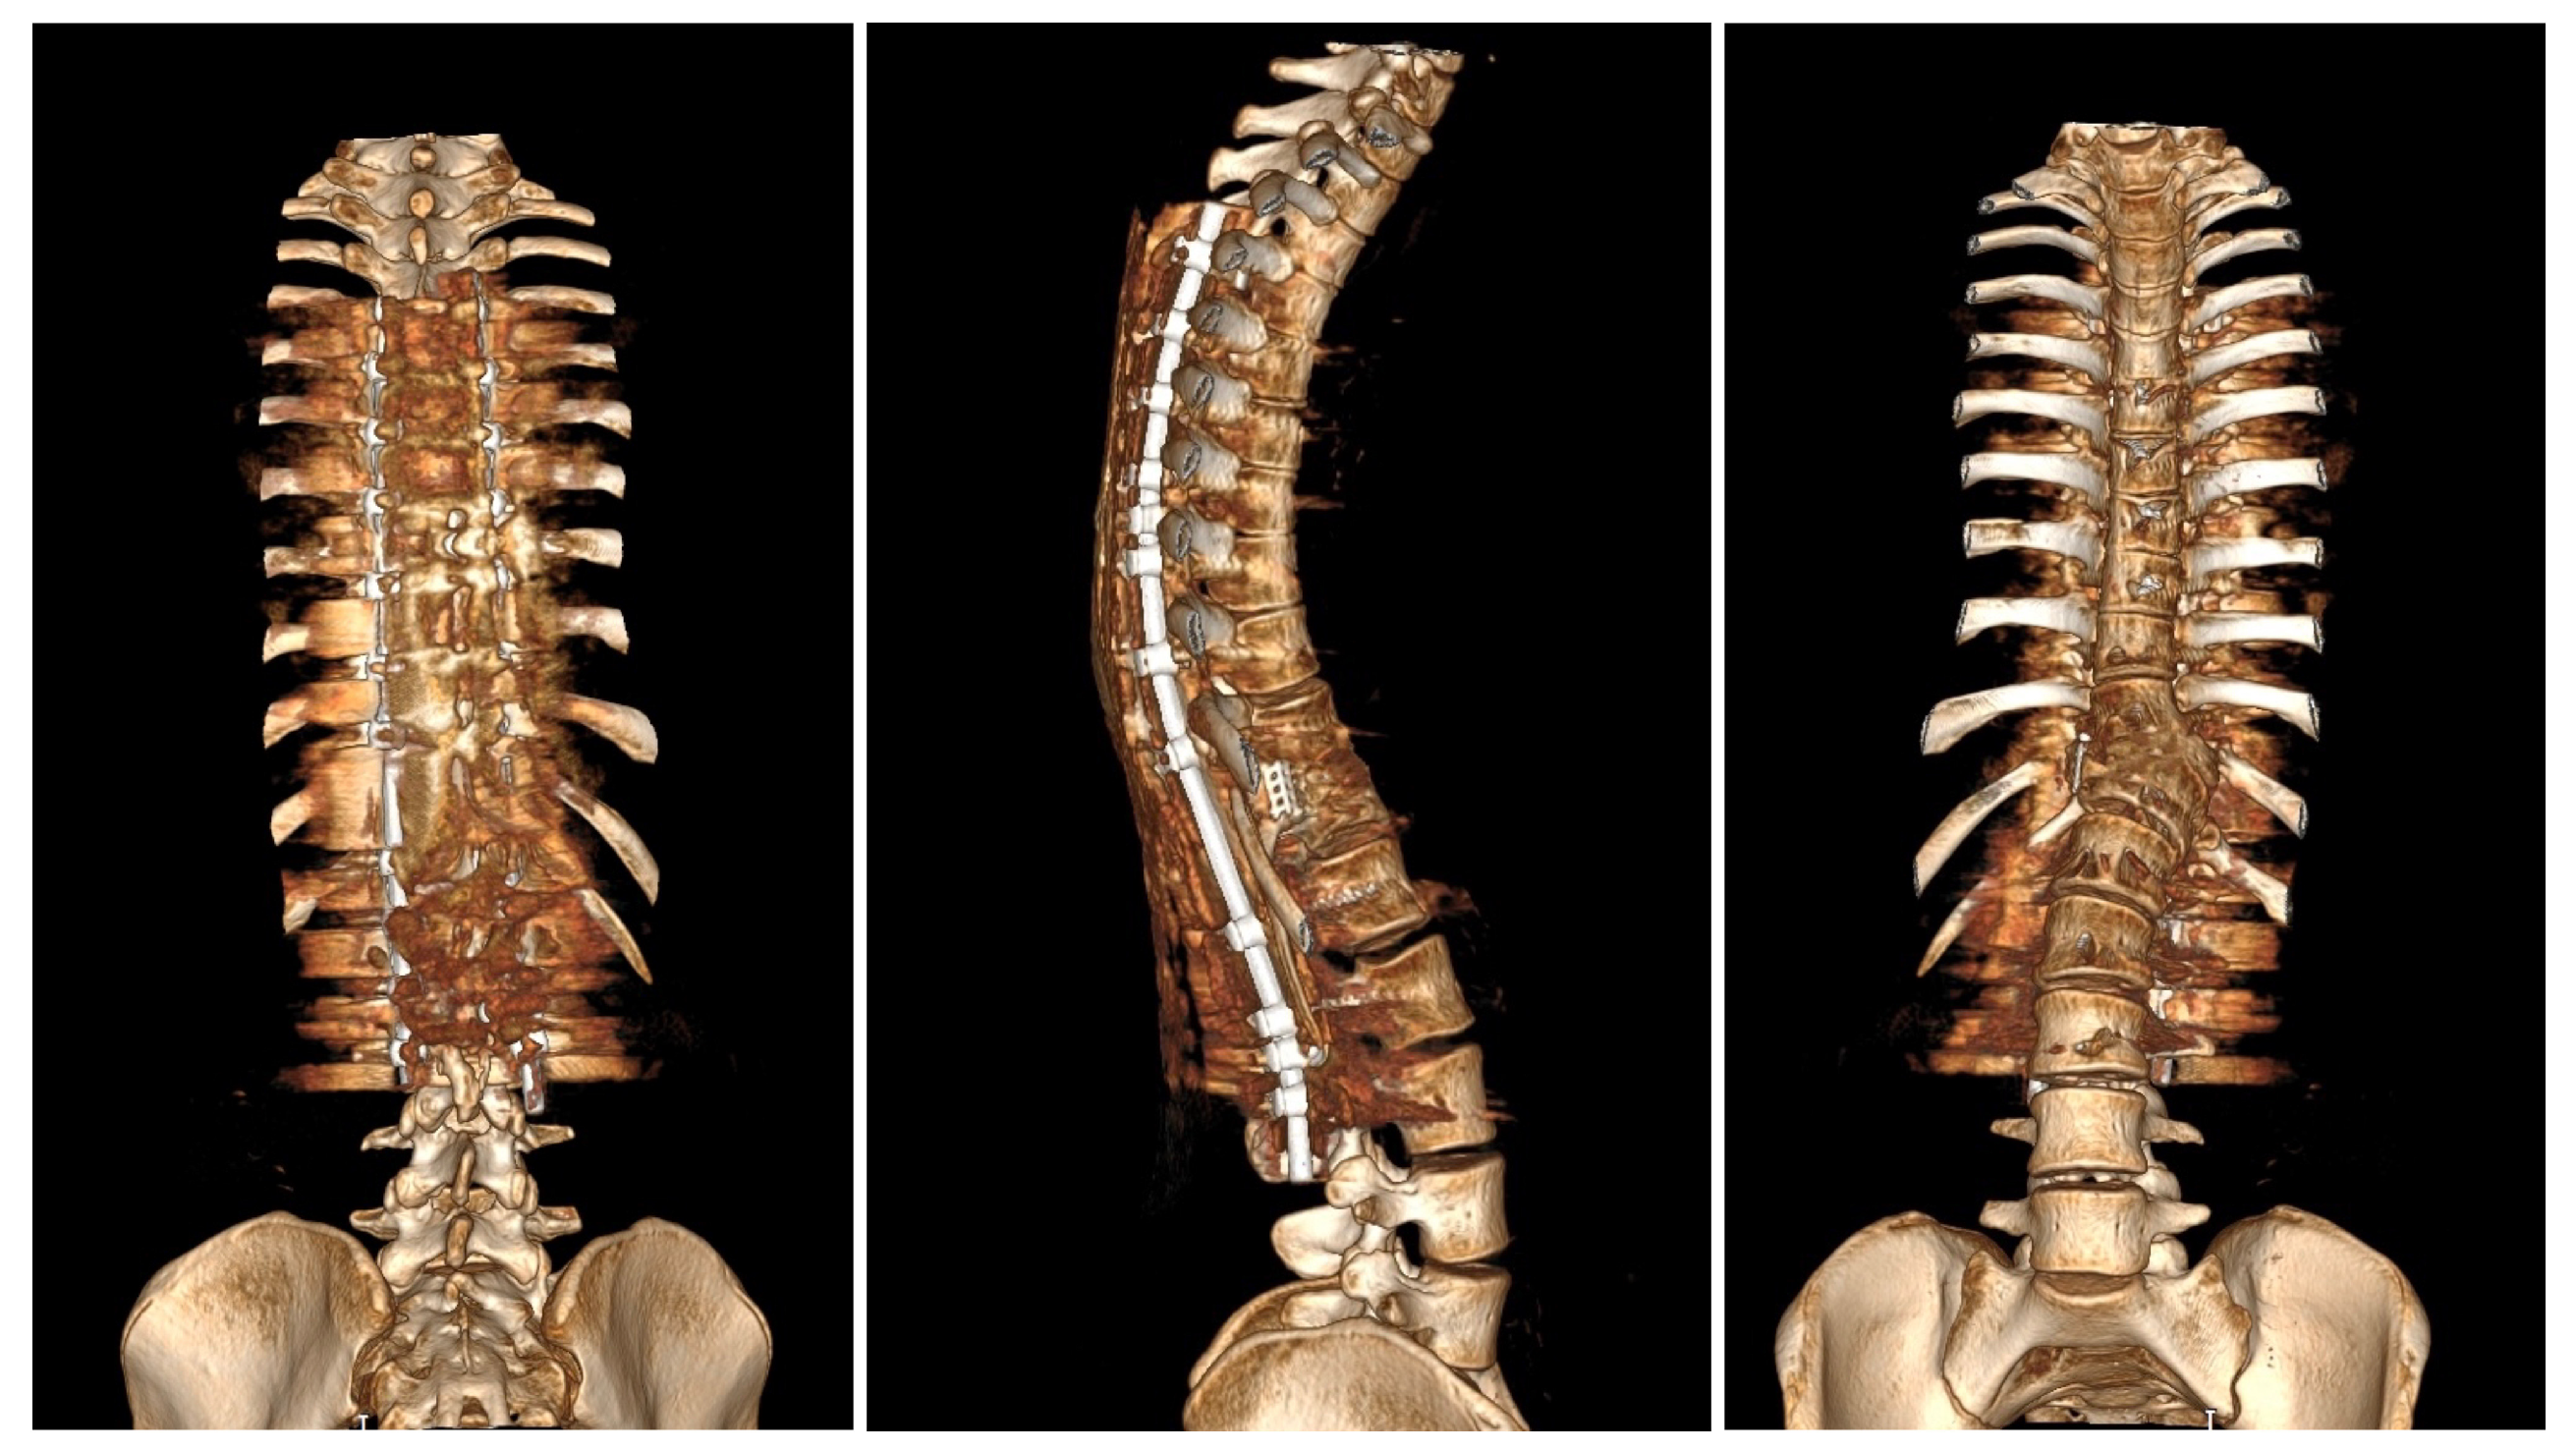

Upon conducting a postoperative physical examination, it was observed that the patient’s shoulder symmetry and rib hump had improved significantly without any neurological or other complications. Figure 9 shows a significant improvement in the patient’s posture, sagittal balance (focal thoracic kyphosis from 108° to 43°), and coronal balance (from 63° to 25°). The patient was discharged 5 days after surgery; no brace was ordered. Figure 10 and Figure 11 show the X-rays and 3D-CT of the patient at the final follow-up.

Figure 11. 3D-computer tomography reconstruction of the whole spine of the 16-year-old female after undergoing surgical treatment at 2 years of follow-up. The pictures show spondylodesis of the posterior and anterior columns.